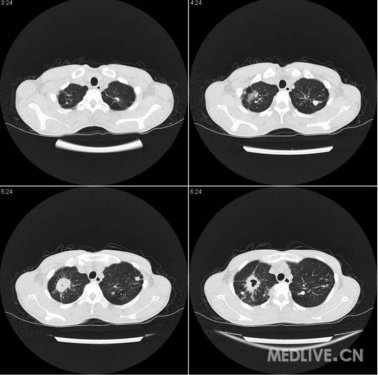

哎呀,这个问题真是让人揪心啊!继发性肺结核,听起来就让人心里一紧。你知道吗,这可不是什么小感冒,随便吃点药就能好的。这种病,它是有原发性的肺结核没治好,然后又卷土重来的。

想象一下,你的肺里有个小恶魔,一开始可能没啥感觉,但慢慢地,它就开始捣乱了,让你咳嗽、咳痰,甚至还会发烧、没力气。这时候,你可不能掉以轻心,以为它会自己好。不,不,不,继发性肺结核可没那么善良。

医生们都说,这病得好好治,得用抗结核的药,得坚持治疗,不能半途而废。要是你不管它,让它自生自灭,那可就麻烦大了。它可能会变得更厉害,甚至传染给别人。

所以啊,亲爱的朋友们,如果你觉得自己有这些症状,赶紧去医院,别拖着。继发性肺结核,它可不会自愈,得靠我们自己,靠医生的帮助,才能。